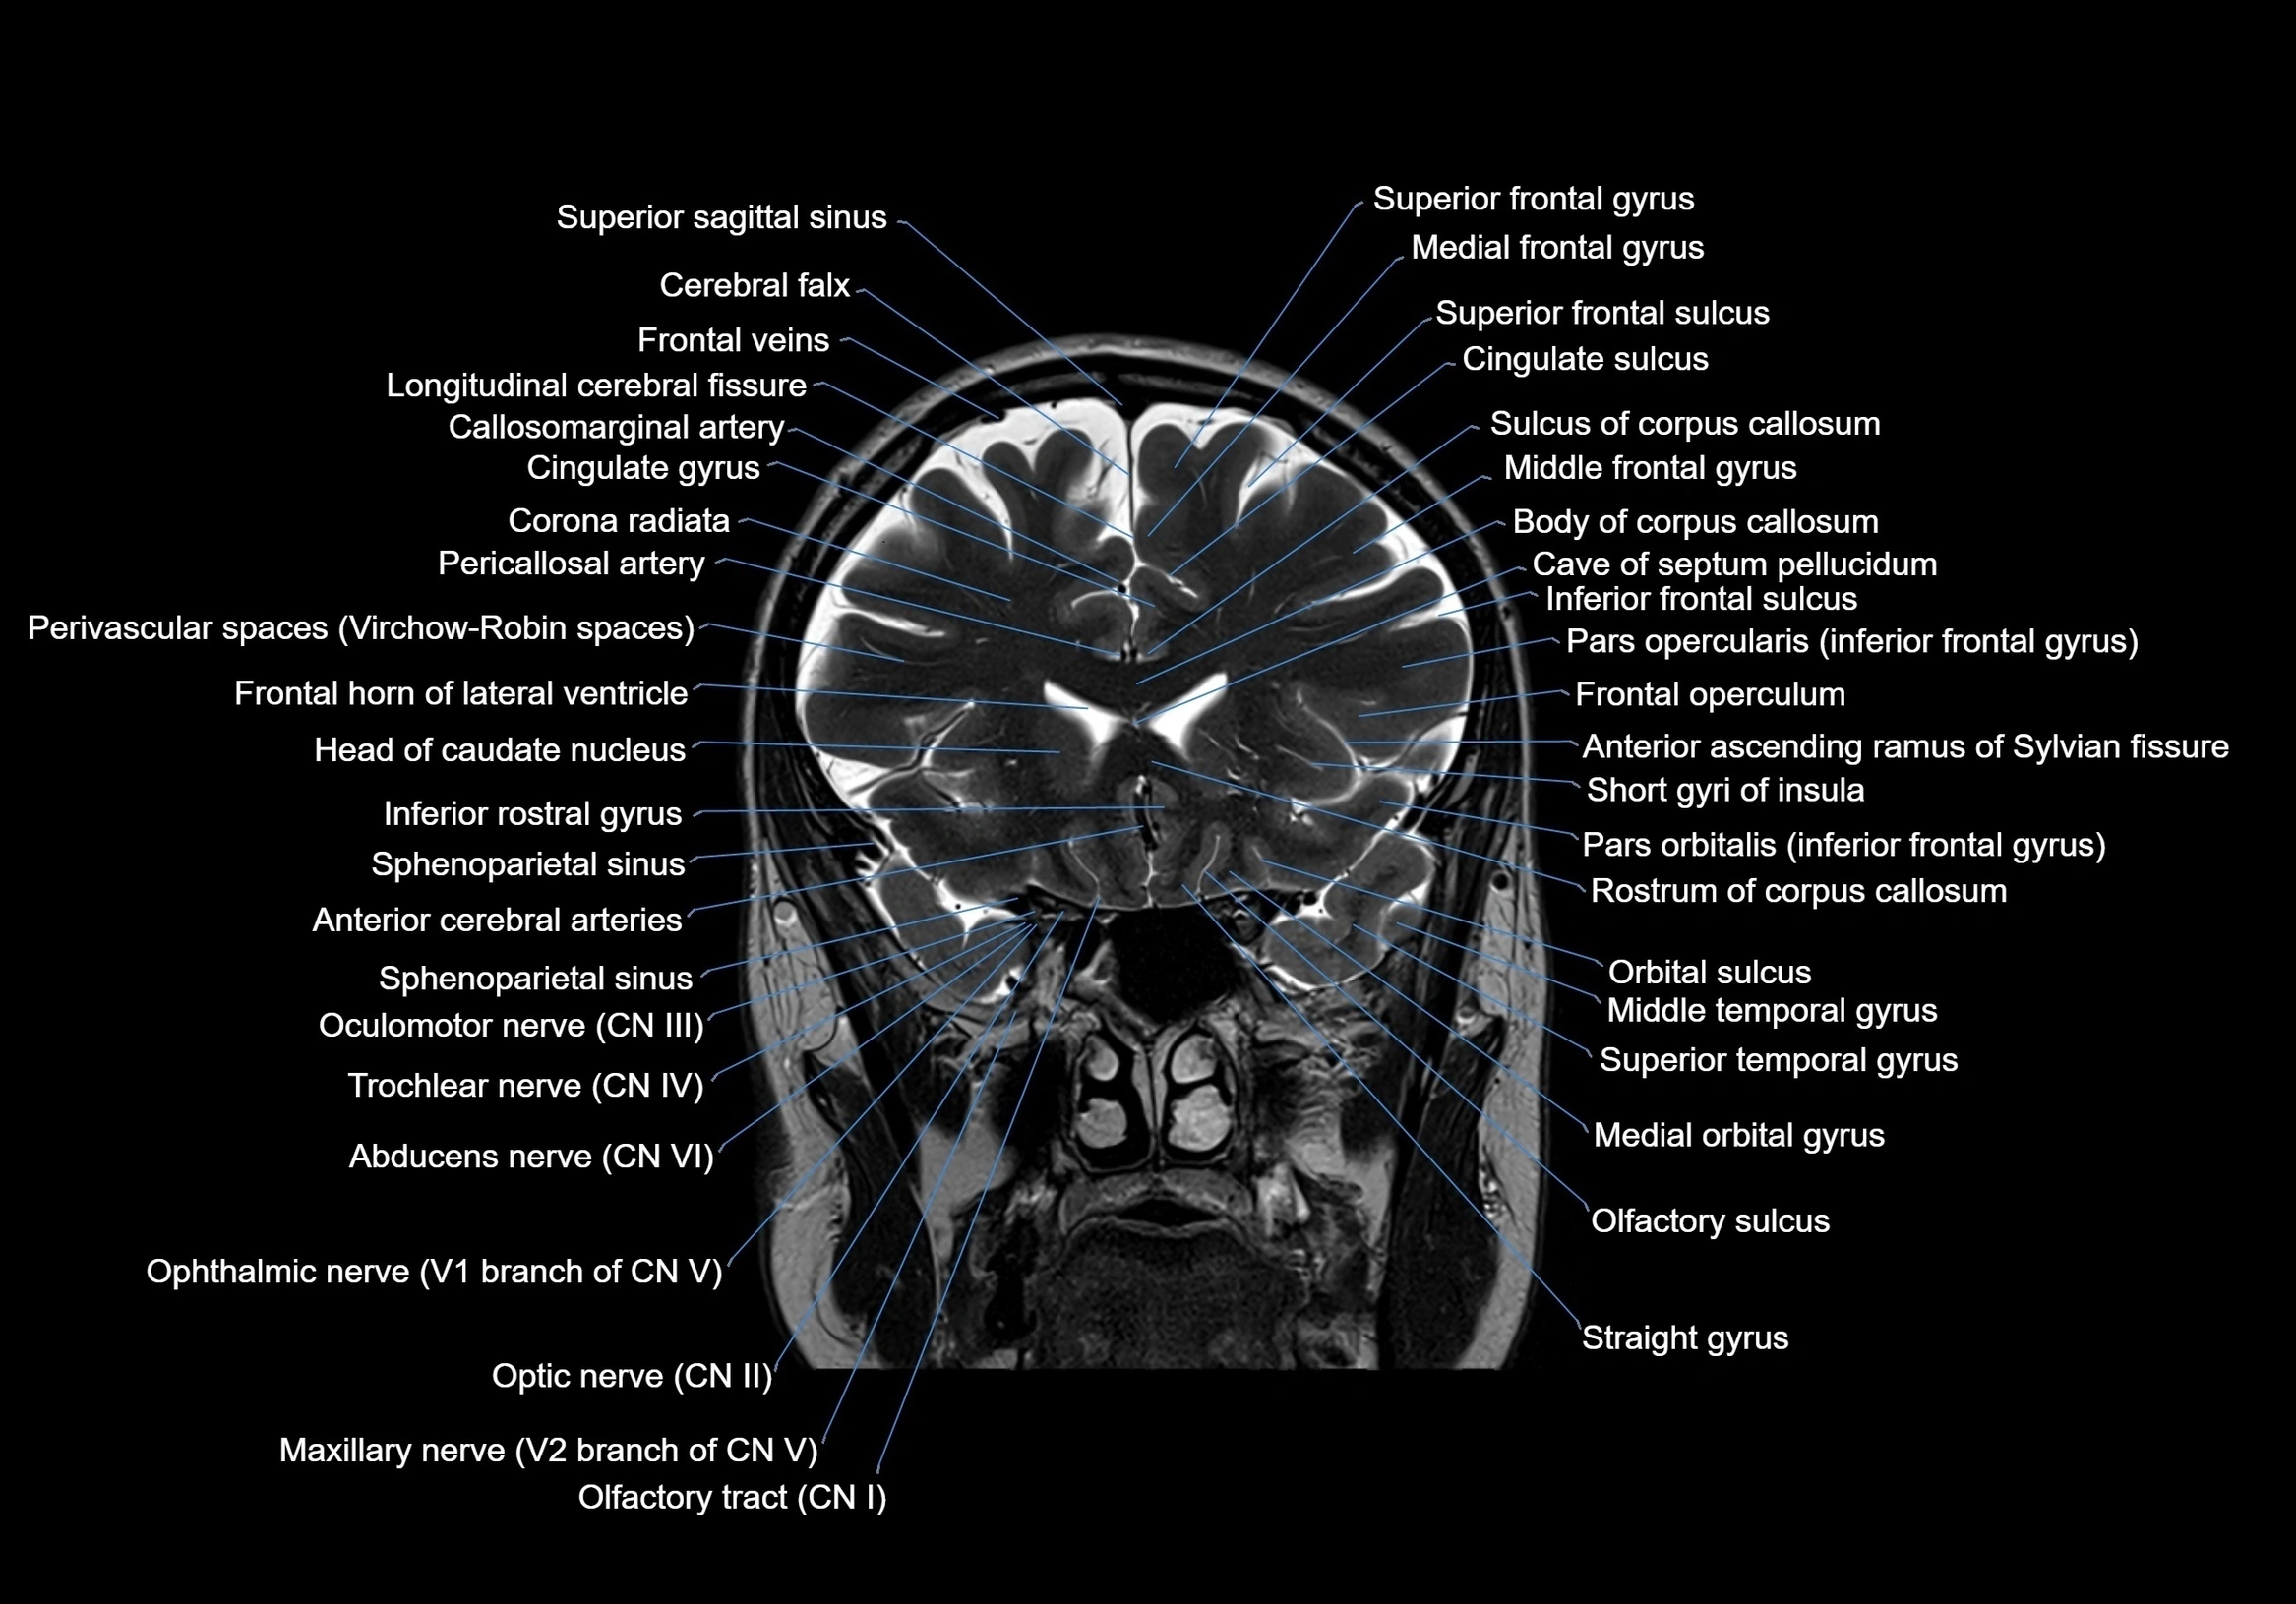

MRI images